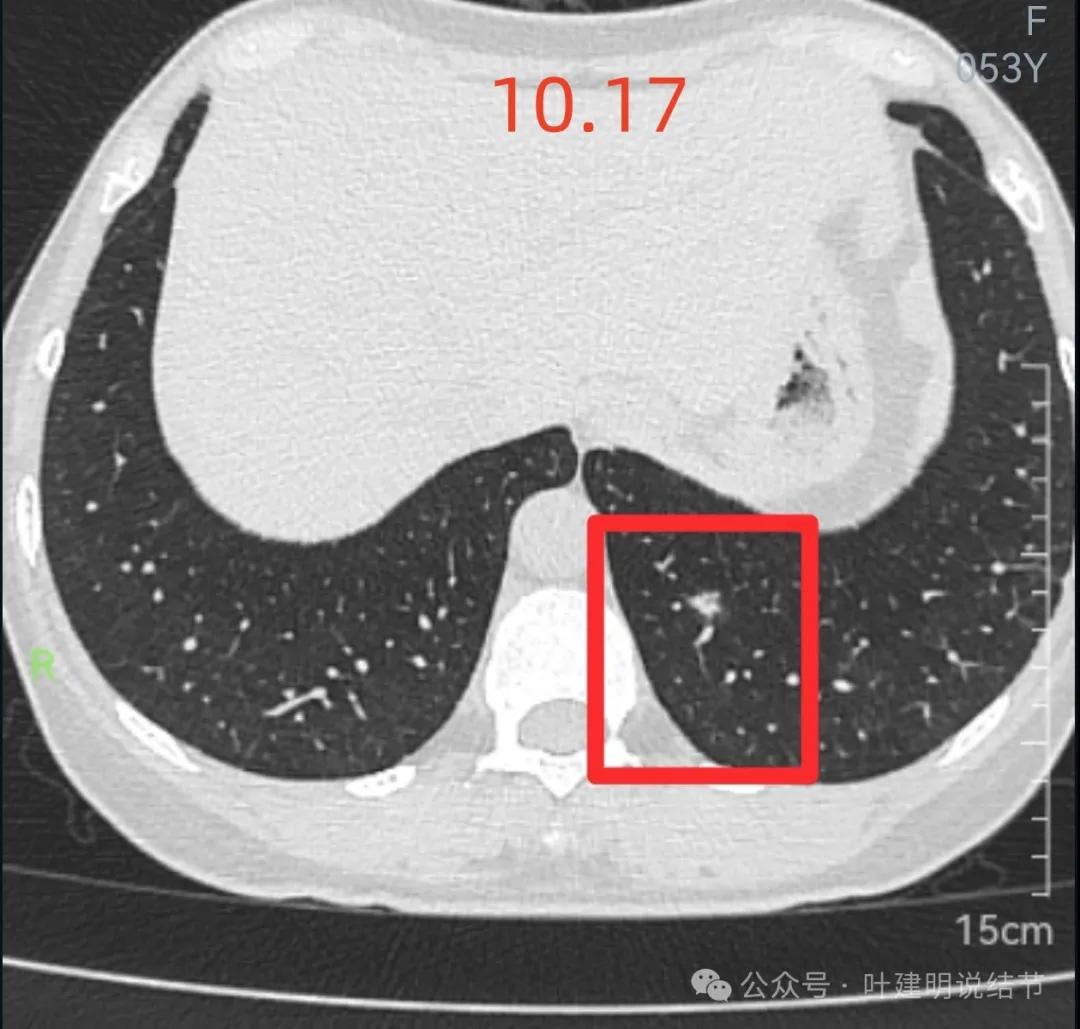

先来看2024年10月16日的影像:

右下叶背段边界欠清的磨玻璃影,有血管刚好位于病灶处。

左下小片状模糊影,轮廓与边界欠清。

左下叶混合密度结节,边缘有淡的磨玻璃影,瘤肺边界欠清,实性成分明显,略偏散。

右下叶以及左下叶实性结节,缺乏膨胀性,没有收缩力,紧贴胸壁或膈肌无牵拉凹陷。

蓝色的是实性的小结节,缺乏膨胀性,两次检查都有,没有变化,考虑是良性的;红色的这些事10月份检查新增的,这两处比较明显的9月份的时候就是绿色框起来这个区域,当时是没有的。短时间内出现、多发病灶、边缘模糊、轮廓欠清,没有恶性特征,与炎性病变符合。建议查查隐球菌方面的化验,如此结果阳性,请呼吸内科或感染科处理。意见供参考!

从连续层面以及影像细节上看,这个病灶就不可能是恶性的!短期内出现,混合密度而瘤肺边界不清,整体缺乏收缩力也无膨胀性,灶内实性成分不致密且磨玻璃成分过淡,灶内血管有异常增粗与密度过高,又是两肺多发病灶。这所有的表现与病情发展都与感染性病变契合,周围淡磨就是炎症水肿的关系,血管异常就是管壁有炎症的关系,多发就是感染(致病因素)影响两肺的关系。怎么可能是恶性?

肺结节看影像考虑良性还是恶性,从细节上分析影像特征当然是很重要的,但在炎性恢复期有时表现的与肿瘤性质的几乎没有区别,我们自己也在这上面吃过亏,明显混合磨玻璃结节约2厘米,没有随访直接切除后是肺泡上皮增生的,回想或许若术前复查一次,病灶大概明显吸收好转了的。今天分享的这个病例,我认为不可能是恶性的,包括4B这处。原因如下:1、间隔20天,从无到有,并表现为混合磨玻璃密度,若是肿瘤性质没有这么快,不符合磨玻璃肺癌的生物学行为的;2、多发病灶短期内出现,更用炎症能够解释,而用肿瘤不能解释;3、所谓主病灶考虑4B的,整体轮廓虽较清,但瘤肺边界偏模糊,磨玻璃成分密度过低而中间实性成分密度较高,却又缺乏收缩力。病灶紧贴叶间裂,但没有任何牵拉,无胸膜凹陷。其实以上这几点就是炎症性的最重要依据。看肺结节,判断良恶性,不能只纠结于影像表现,要有综合观、全局观,要考虑临床上是否解释得通。